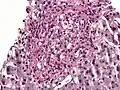

Histoplasma. PAS diastase stain.

Histoplasma. PAS diastase stain. Histoplasma in a granuloma. PAS diastase stain.